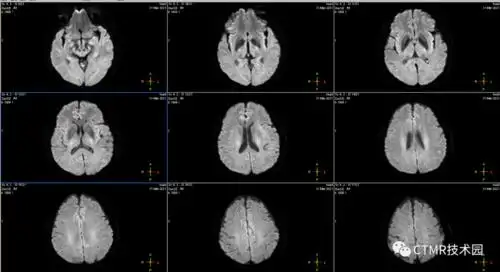

手把手教你基础颅脑mr平扫及后处理